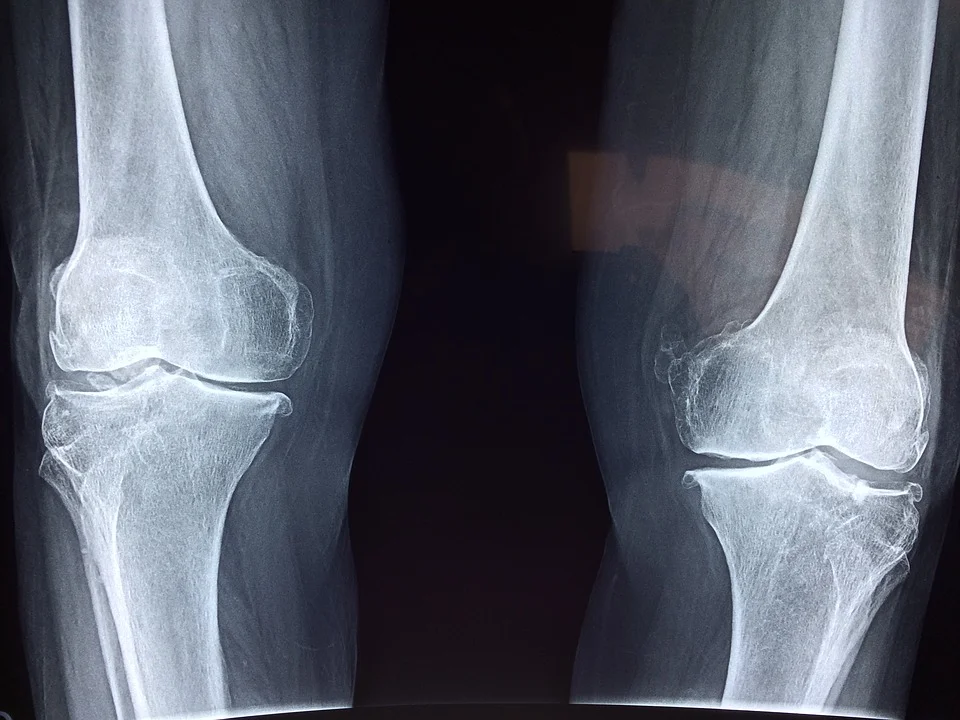

Silne kości na długie lata – jak zapobiegać urazom i zwyrodnieniom

Z wiekiem układ kostny i stawowy traci elastyczność, a ryzyko urazów i schorzeń jak osteoporoza wzrasta. Aby temu zapobiegać, warto zadbać o dietę bogatą w wapń, witaminę D […]